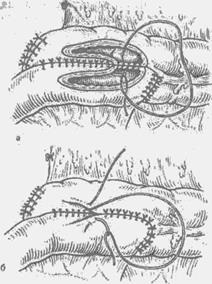

A anastomosis vittük kétsoros nodális-kovymi varratok a szokásos módon (ábra. 15, b). Végén az overlay ileotransverzoanastomoza első vagy a második módon vannak varrva szélén bélfodra a vastagbél és a vékonybél. Távolítsuk el a hiba a hátsó fal Bru busz térhálósításával folyamatos catgutból élek Bru busz mentén oldalcsatornás (ábra. 15c).

Benyújtásának eltávolítását a vastagbél mellékelt dréncső bevezetésére antibiotikumok. A csövet visszahúzzuk egy külön metszést a jobb csipő vagy lumbalis régió, és rögzítve van a bőrre. Laparotomia seb zashi-vayut rétegek. A nem megfelelő béieiőkészités ürítésére előtt varrókészülék az anasztomózis hasi laza vége a vastagbél, hogy az anastomosis kiadásra kerül a hasfal elülső egy bemetszésen keresztül a jobb meghajlítani a megfelelő szintre, ahol az alakított vége vastagbélsipoly. 2-3 hét elteltével colostomia zárva van, a hashártya által m # 1205 stnoy érzéstelenítés. Kirakodásához anasztomózis is bevezetett széles cső a végén a vastagbél proximális és a anasztomózis (Bear - Brown - Kyum szálú) (ábra 15 g.).

Ábra. 15. előírása ileotransverzoanastomoza CO-Heff oldalán.

és - alakítás a hátsó fal-ki; b - képező elülső fal; in - elvezetését Zabra busz-tér-sósav dréncső záródási rendellenességek hátsó parietális peritoneum:

g - a bevezetése a végén a cső a vastagbél bél kirakodás ana-stomoza.